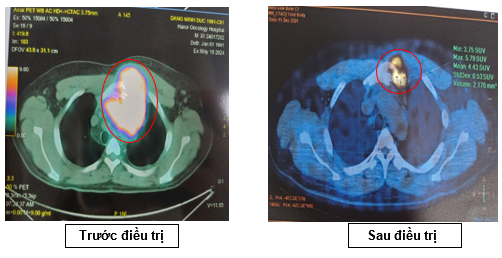

-         Hình ảnh chụp PET/CT đánh giá giai đoạn trước điều trị (tháng 5/2024)

·        Hạch nền cổ, thượng đòn 2 bên, lớn nhất ~ 28x18mm (SUVmax: 10.47).

·        Khối lớn ở trung thất trước, lệch trái kích thước ~84x109x90mm, phá hủy xương ức,cung trước xương sườn 3 trái, thành ngực trước trái, xâm lấn quai động mạch chủ (SUVmax: 17.88).

·        Vài hạch trung thất, lớn nhất 14x17mm (SUVmax: 3.17). Hạch rốn gan, hạch bẹn. Tăng nhẹ chuyển hóa FDG lan tỏa ở hệ thống xương.

Hình 2: Hình ảnh tăng chuyển hoá FDG ở nhiều vị trí khối lớn ở trung thất trước, hạch cả ở trên và dưới cơ hoành, tăng FDG lan tỏa hệ thống xương.

Hình 3: Khối lớn ở trung thất trước, lệch trái kích thước ~84x109x90mm, phá hủy xương ức

Nhận xét: Sau 06 chu kỳ điều trị, khối trước xương ức giảm kích thước (từ 109x90mm còn 57x45 mm, trước điều trị SUVmax: 17,88 -> sau điều trị SUVmax 5,79). Hạch cổ, hạch thượng đòn, hạch bẹn, hạch rốn gan không còn nhìn thấy trên phim PET/CT, không tăng chuyển hoá FDG -> PET/CT sau 6 chu kỳ hóa trị: Đáp ứng một phần (PR) theo tiêu chuẩn Lugano 2014.